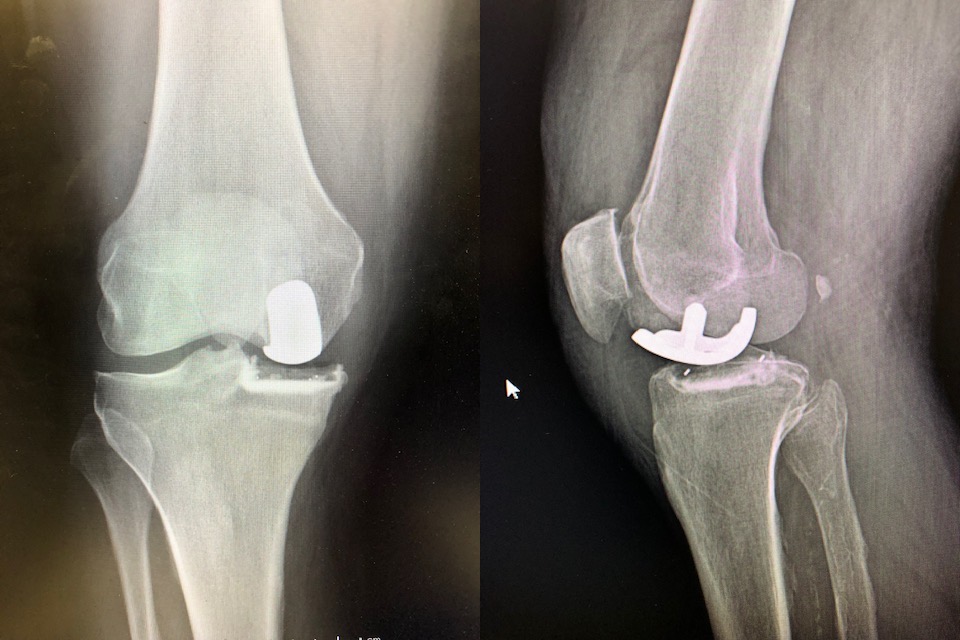

The Freedom knee, formerly the Repicci, that I use is a minimally invasive RESURFACING implant with minimal bone removal. Most partial knees done today remove more bone and look like half of a total knee replacement, they are called RESECTION partial knees. Here are some xrays to illustrate the difference

Primary total knee replacement after Repicci resurfacing PKR (right)